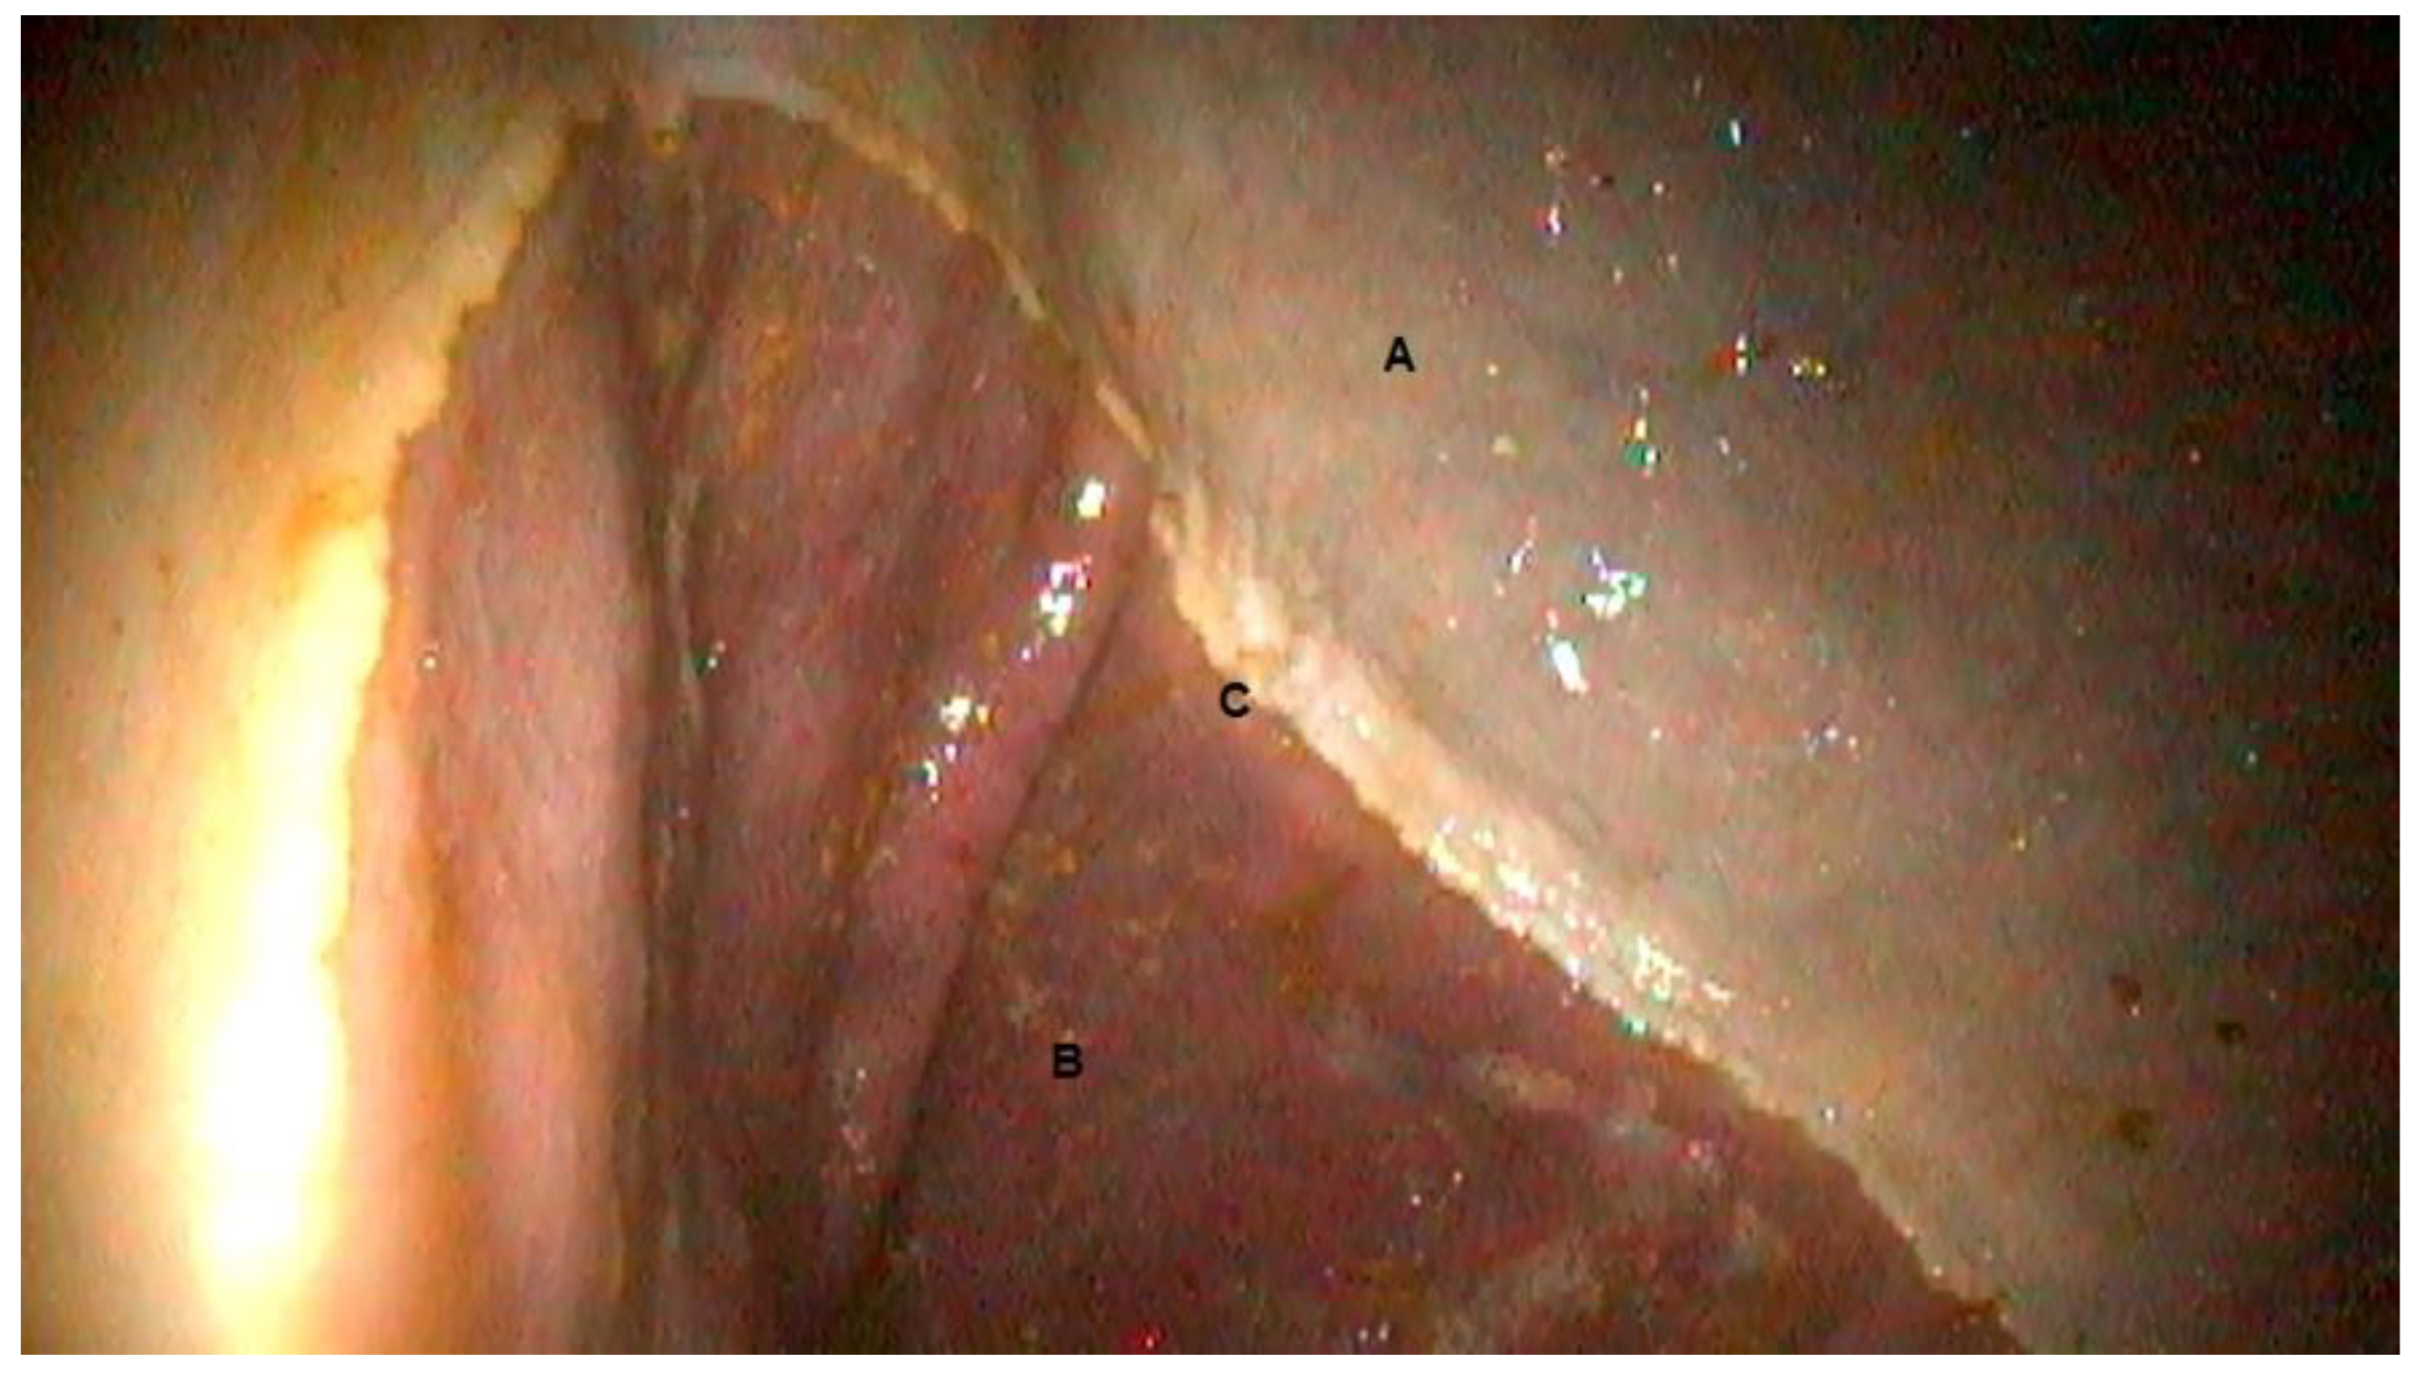

3.1. Gastroscopic Evaluation